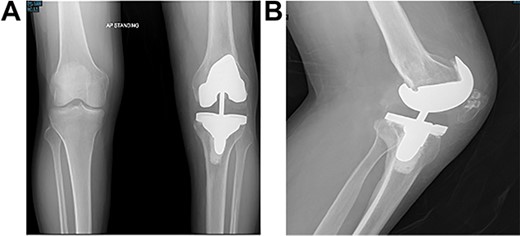

Post-operative plain radiographs from follow-up visits; (A) 3-month post-operative AP radiograph showing implant in place with a lateral gap sized to be 3.2 cm; (B) 3-month post-operative lateral radiograph of the knee showing implant in a satisfactory position.

At the 2-year follow-up visit, the patient’s active ROM continued to be between 4 and 85° (Fig. 7). Patient’s functional outcome score was measured using the Knee Injury and Osteoarthritis Outcome Score pre- and post-operatively, with marked improvement in scores noted from 45 to 76%.